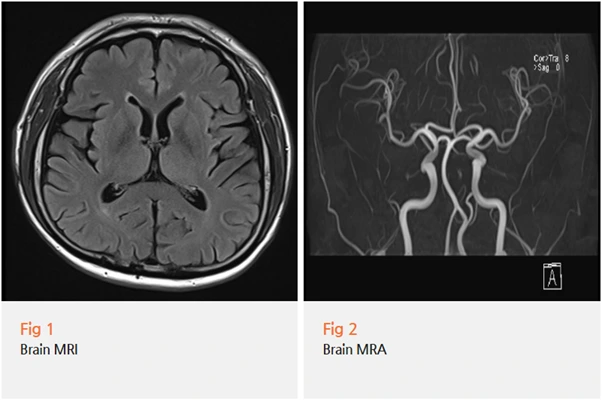

저는 우선 뇌 쪽 기질적 문제를 배제하기 위해 뇌 MRI와 MRA 검사를 진행했어요.

안면부와 두경부에 걸친 통증과 감각 이상은 드물지만

뇌신경 병변에서도 나타날 수 있기 때문에,

이 부분을 먼저 확인하는 게 순서입니다.

검사 결과, 다행히 뇌에는 이상이 없었어요.